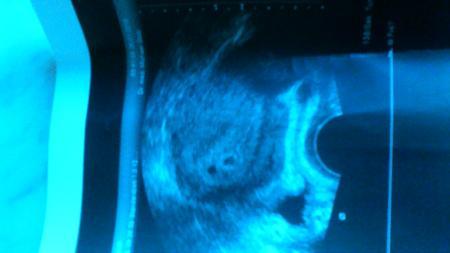

Zwillinge sind es 5+2

Bild zu

heeey... na herzlichen Glückwunsch! ;) Dann hat es ja diesmal schon hingehauen mit dem hohen hcg-Wert. Ich wünsch dir eine schöne Kugelzeit! Wird sicher nochmal ne tolle Erfahrung mit den beiden!